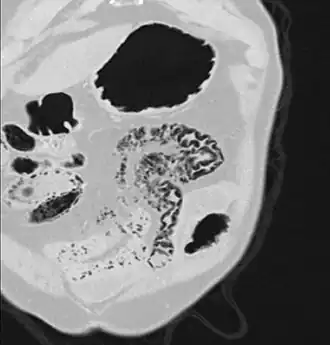

Close-up of intestine of infant showing necrosis and pneumatosis intestinalis (autopsy) | |

Pneumatosis intestinalis at computed tomography in intestinal ischemia. Lung window for better representation of the gas deposits in the intestinal walls. Coronal reconstruction.